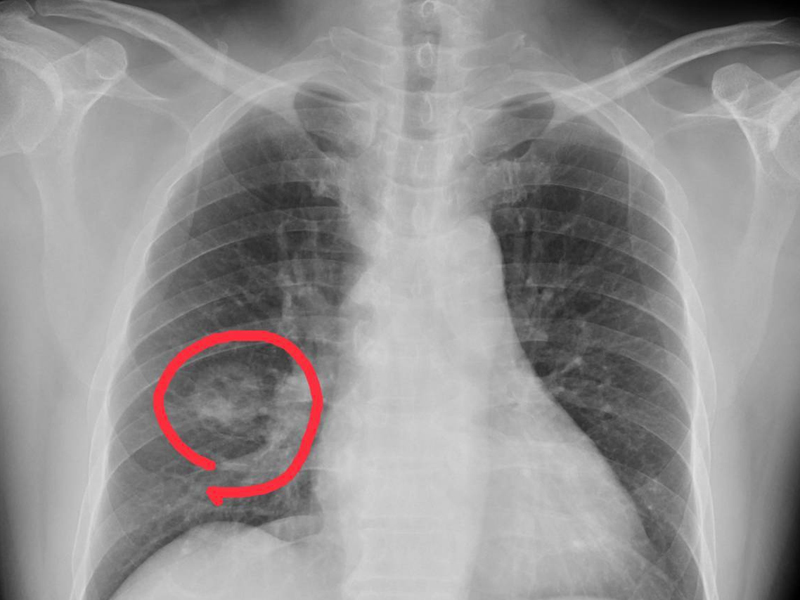

肺癌來臨並非無聲無息,提醒:手腳出現 4 種異常,可能是肺癌到來,不要大意!

1. 手指變粗

一般情況下手指變粗很可能是肺癌的信號,尤其是長期吸煙的男性朋友,要特別警惕杵狀指,也就是手指末端變粗,增生,膨大,同時還會伴有咳血、刺激性乾咳、胸痛等症狀。